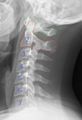

في البشر، الفقرات العنقية تكون أصغر من الفقرات الحقيقية، ويمكن تمييزها بسرعة عن الفقرات الصدرية أو القطنية حيث توجد الثقبة (فتحة) في كل نتوء مستعرض، والتي يمر من خلالها الشريان الفقري.

يكون جسم الفقرة العنقية أصغر من جسم الفقرة الصدرية، وذلك لأن الوزن الذي يتحمله أقل من الوزن الذي تتحمله الفقرة الصدرية. وشوكة الفقرة العنقية تكون أصغر ومشقوقة أيضاً. أما النتوء المستعرض ففيه ارتفاع أمامي وخلفي. في بعض البشر يكون هناك ضلع عنقي مرتبط بالفقرة العنقية السابعة وقد يسبب انسداد للشرايين والأوردة والأعصاب وكل الأعراض الناتجة من ذلك.